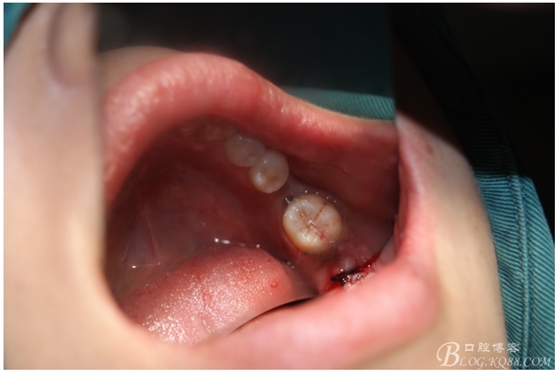

處理:必蘭麻局部麻醉切開37遠(yuǎn)中牙齦,植入mini支抗釘一枚,37近中鄰面粘舌側(cè)扣,皮鏈輕力牽引,3周更換。

三月后37扶正